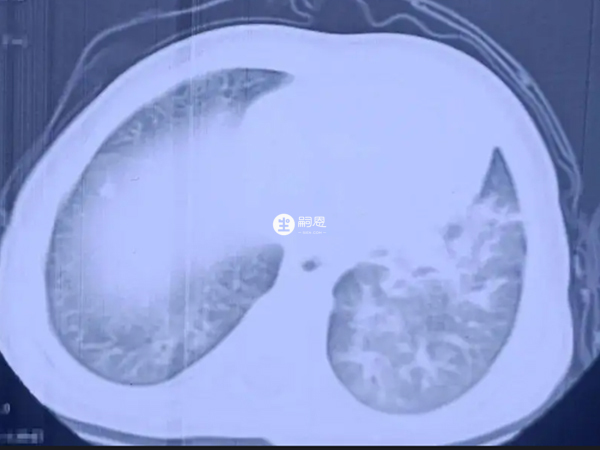

十個新生兒拍ct九個都是肺部感染本身就是一個概率問題,並不能說明新生兒肺部感染是普遍存在的,往往是恰巧出現的十個新生兒九個肺部感染這個結果。新生兒肺部感染就是指新生兒肺炎,而新生兒肺炎又分為吸入性肺炎和感染性肺炎,吸入性肺炎是胎兒在宮內或生產時吸入了大量羊水所致,感染性肺炎在宮內、分娩時以及生產後都可能發生,可由不同病原體引起。

新生兒肺部感染其實發生率還是比較高,但是也沒有像十個新生兒拍ct九個都是肺部感染這麼高,因為十個新生兒九個肺部感染這個說法本身就是不嚴謹的,這是概率問題,而新生兒肺部感染是有原因的,不能混為一談。下面就為大家介紹一下新生兒肺部感染是怎麼一回事: